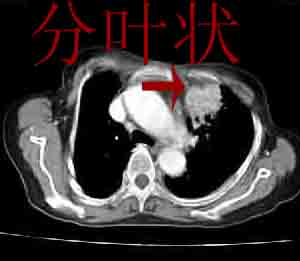

左上肺前段可见分叶团块影,强化明显,周围见带状不张影,右肺结节,左肺沿肺纹模糊片状影,考虑左上肺占位,肺癌可能性大。